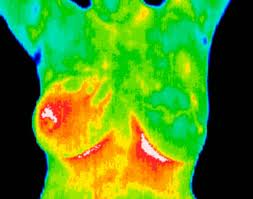

Inflammatory carcinomas are breast cancer tumors that are diagnosed as very serious and really spread very quickly. They manifest themselves through warmth of the skin, redness, and swelling. With this, these breast cancer tumors are often mistaken for mastitis. Inflammatory sarcoma is mainly caused by the breast cancer tumors that block the lymph nodes. Many women have already died from inflammatory sarcoma.